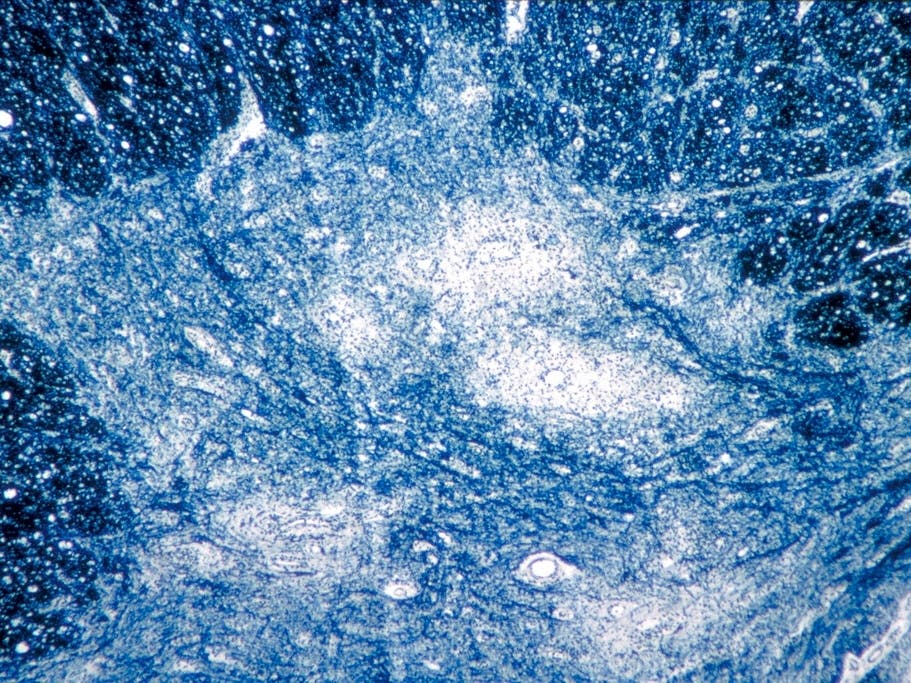

Polio spreads mostly from person to person or through contaminated water. It can infect a person’s spinal cord, causing paralysis and possibly permanent disability and death.